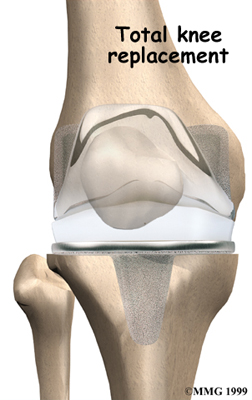

Artificial Knee Replacement

An artificial knee replacement is the ultimate solution for advanced knee OA.

Surgeons prefer not to put a new knee joint in patients younger than 60. This is because younger patients are generally more active and might put too much stress on the joint, causing it to loosen or even crack. A revision surgery to replace a damaged prosthesis is harder to do, has more possible complications, and is usually less successful than a first-time joint replacement surgery.

Related Document: FYZICAL Ruston's Guide to Artificial Joint Replacement of the Knee